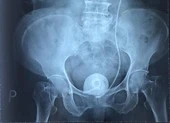

Kết quả siêu âm và chụp cắt lớp vi tính hệ niệu ghi nhận thận trái ứ nước độ II, sỏi vùng bể thận – niệu quản bên trái, sỏi bàng quang, có 1 đoạn ống thông JJ trong cả 2 viên sỏi.

Tiến hành phẫu thuật nội soi, bác sĩ lấy ra 1 viên sỏi kích thước 3.5 cm, khâu thận, niệu quản và 1 viên sỏi to trong bàng quang, kích thước 9 cm.

Tổng trọng lượng 2 viên sỏi là 300 grs.